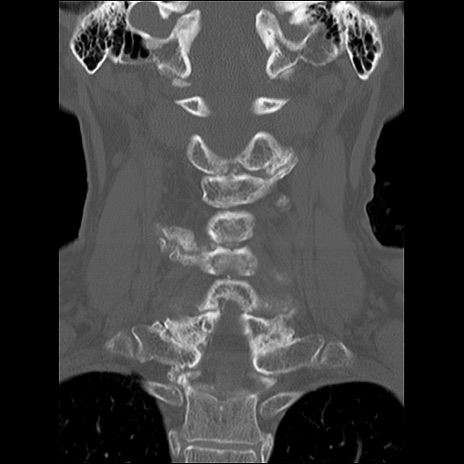

症例48 頚椎CT(冠状断像)

頚椎CT